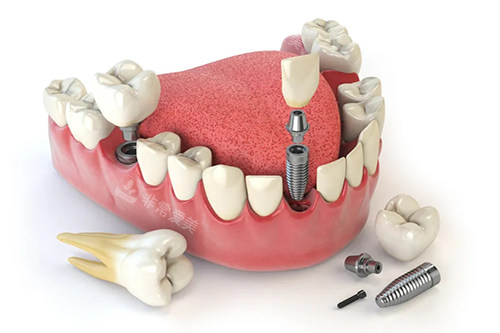

牙齿种植卡通示意图

单颗牙齿种植示意图

贝格口腔的种植技术成熟度极高。

一方面,医生们拥有丰富的临床种植经验,对于各种复杂的种植术例都能制定出个性化的治疗方案。

他们熟练掌握多种种植系统的操作,能够根据患者的口腔条件和需求,选择较适合的种植体,确保种植结果的稳定性和持久性。